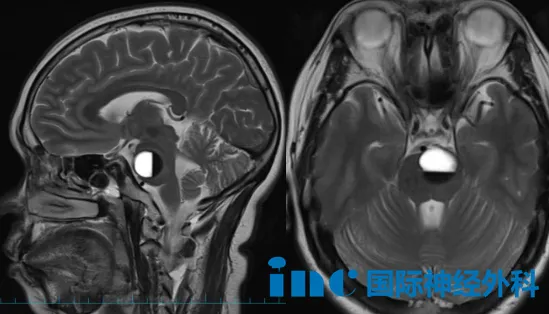

患者3:宇轩(27岁)

年仅二十七岁的宇轩,因脑干海绵状血管瘤突发出血,病情危急,手术已迫在眉睫。术前谈话结束后,父母激动难抑,泪水止不住地流,哽咽着说:"感谢巴教授给孩子一个救命的机会!"